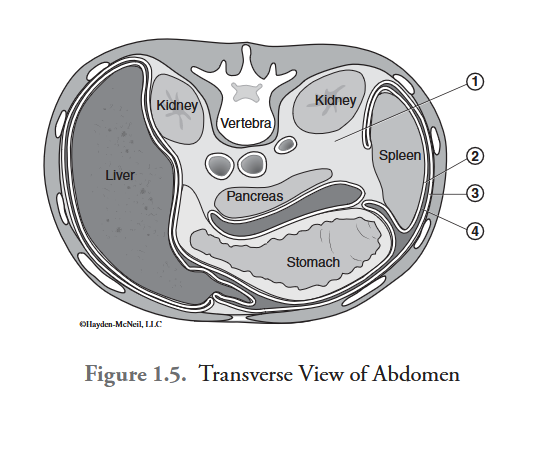

What is labeled #1?

retroperitoneal space

What is labeled #2?

visceral peritoneum

What is labeled #3?

parietal peritoneum

What is labeled #4?

peritoneal cavity